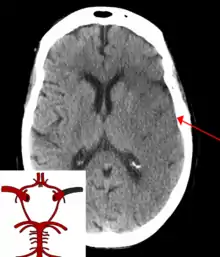

السكتة الدماغية أو السكتة أو الحادثة الدماغية الوعائية (بالإنجليزية: Cerebrovascular accident) أو الجلطة الدماغية، هي عند نقص تدفّق الدم وتغذيته إلى أحد أجزاء الدماغ والذي يؤدي إلى موت الخلايا. هناك نوعان رئيسيان من السكتة الدماغية،: السكتة الدماغية الإقفارية، وهي بسبب نقص تدفق الدم، والسكتة الدماغية النزفية، وهي بسبب النزيف الدماغي.[4] يؤدي هذا إلى ألّا يعمل جزء من الدماغ بشكل سليم.[5][6] وقد تشمل علامات وأعراض السكتة الدماغية عدم القدرة على تحريك أو الشعور بأحد أطراف الجسم، ومشاكل الفهم أو الكلام، والشعور بالدوران، وعدم القدرة على رؤية جانب واحد من المجال البصري. غالبًا ما تظهر الأعراض خلال وقت قصير من حدوث السكتة الدماغية. إذا استمرت الأعراض لأقل من ساعة أو ساعتين تُعرَّف الحالة كنوبة نقص تروية عابرة.[6] قد يرافق السكتة الدماغية النزفية صداع شديد.[6] قد تكون أعراض السكتة الدماغية دائمة وقد تشمل المضاعفات طويلة الأمد الالتهاب الرئوي أو فقدان السيطرة على المثانة البولية.[6]

عامل الخطر الرئيسي للسكتة الدماغية هو فرط ضغط الدم.[7] وتشمل عوامل الخطر الأخرى التدخين، والسمنة، وارتفاع نسبة الكوليسترول في الدم، داء السكري، نوبة نقص تروية عابرة سابقة، والرجفان الأذيني وغيرها.[5][7] تنتج السكتة الدماغية الإقفارية من انسداد أحد الأوعية الدموية، أما السكتة الدماغية النزفية فتنتج من نزيف إما مباشرة للدماغ أو للفراغ المحيط بالدماغ.[8][9] قد يحدث النزيف نتيجة لأمهات الدم الدماغية.[8] عادة ما يتم التشخيص باستخدام التصوير الطبي مثل التصوير المقطعي المحوسب أو التصوير بالرنين المغناطيسي بالإضافة للفحص السريري. يتم القيام بفحوصات أخرى مثل تخطيط كهربية القلب وفحوصات الدم لتقدير عوامل الخطر واستبعاد أسباب محتملة أخرى. قد يؤدي نقص سكر الدم إلى أعراض مشابهة.[10]

يمكن تصنيف السكتات الدماغية إلى فئتين رئيسيتين: إققارية ونزفية.[13] تنتج السكتات الدماغية الإقفارية من اضطراب في تدفّق الدم إلى الدماغ، بينما تنتج سكتات الدماغ النزفية من تمزّق أحد الأوعية الدموية أو بنية غير طبيعية للأوعية الدموية. حوالي %87 من السكتات الدماغية هي إقفارية، والباقي نزفية. قد يتطور كذلك النزيف خلال المناطق الداخلية من الإقفار، وهي حالة تُعرف باسم "التحوُّل النزيفي". من غير المعروف ما هي نسبة السكتات الدماغية النزفية التي تبدأ كسكتة دماغية إقفارية.[5]

هناك نوعان رئيسيان من السكتة الدماغية النزفية:[23]

1) نزيف داخل المخ، وهو نزيف داخل الدماغ نفسه (عندما ينفجر شريان في الدماغ، يغمر الأنسجة المحيطة بالدم)، إما بسبب نزيف داخل القصبة (نزيف داخل أنسجة المخ) أو نزيف داخل البطين (نزيف داخل البطين).

2) نزيف تحت العنكبوتية، وهو نزيف يحدث بشكل أساسي خارج أنسجة المخ ولكن لا يزال داخل الجمجمة، وبالتحديد بين الأم العنكبوتية وأم حنون (الطبقة الأعمق الحساسة للطبقات الثلاث من السحايا التي تحيط بالمخ).

النزيف داخل الجمجمة هو تراكم الدم في أي مكان داخل قبو في الجمجمة. الأنواع الرئيسية من النزيف داخل الجمجمة هي ورم دموي فوق الجافية (النزيف بين الأم الجافية والجمجمة)، ورم دموي تحت الجافية (في الفضاء تحت الجافية) ونزيف تحت العنكبوتية (بين أم عنكبوتية والأم الحنون). ونزيف في المخ ونزيف داخل أنسجة المخ. ونزيف المخ يمكن أن يكون إما بسبب نزيف داخل المخيخ أو النزيف داخل البطيني (الدم في نظام البطين). معظم متلازمات السكتة الدماغية النزفية لديهم أعراض محددة وخاصة الصداع، أو أن يكون دليلا على وجود إصابة سابقة في الرأس).[24]